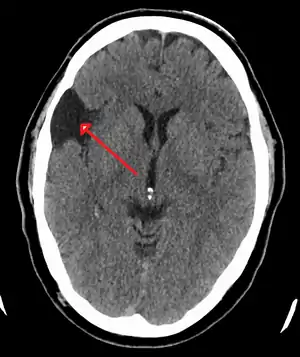

| A CT scan of an arachnoid cyst | |

The diagnostic process typically begins with a medical history workup followed by a medical examination by a physician. Imaging tests, such as CT scans and MRIs, help provide a clearer picture. The physician typically looks for fluid (or other bodily substance) filled sacs to appear in the scans, as is shown in the CT scan of a colloid cyst. A primary health care provider will refer an individual to a neurologist or neurosurgeon for further examination. Other diagnostic methods include radiological examinations and macroscopic examinations. After a diagnosis has been made, immunohistochemistry may be used to differentiate between epithelial cysts and arachnoid cysts.[2] These examinations are useful to get a general idea of possible treatment options, but can be unsatisfactory to diagnose CNS cysts.[3][5] Professionals still do not fully understand how cysts form; however, analyzing the walls of different cyst types, using electron microscopes and light microscopes, has proven to be the best diagnostic tool. This has led to more accurate cyst classification and correct course of action for treatments that are cyst specific. In the past, before imaging scans or tests were available, medical professionals could only diagnose cysts via exploratory surgery.[2]